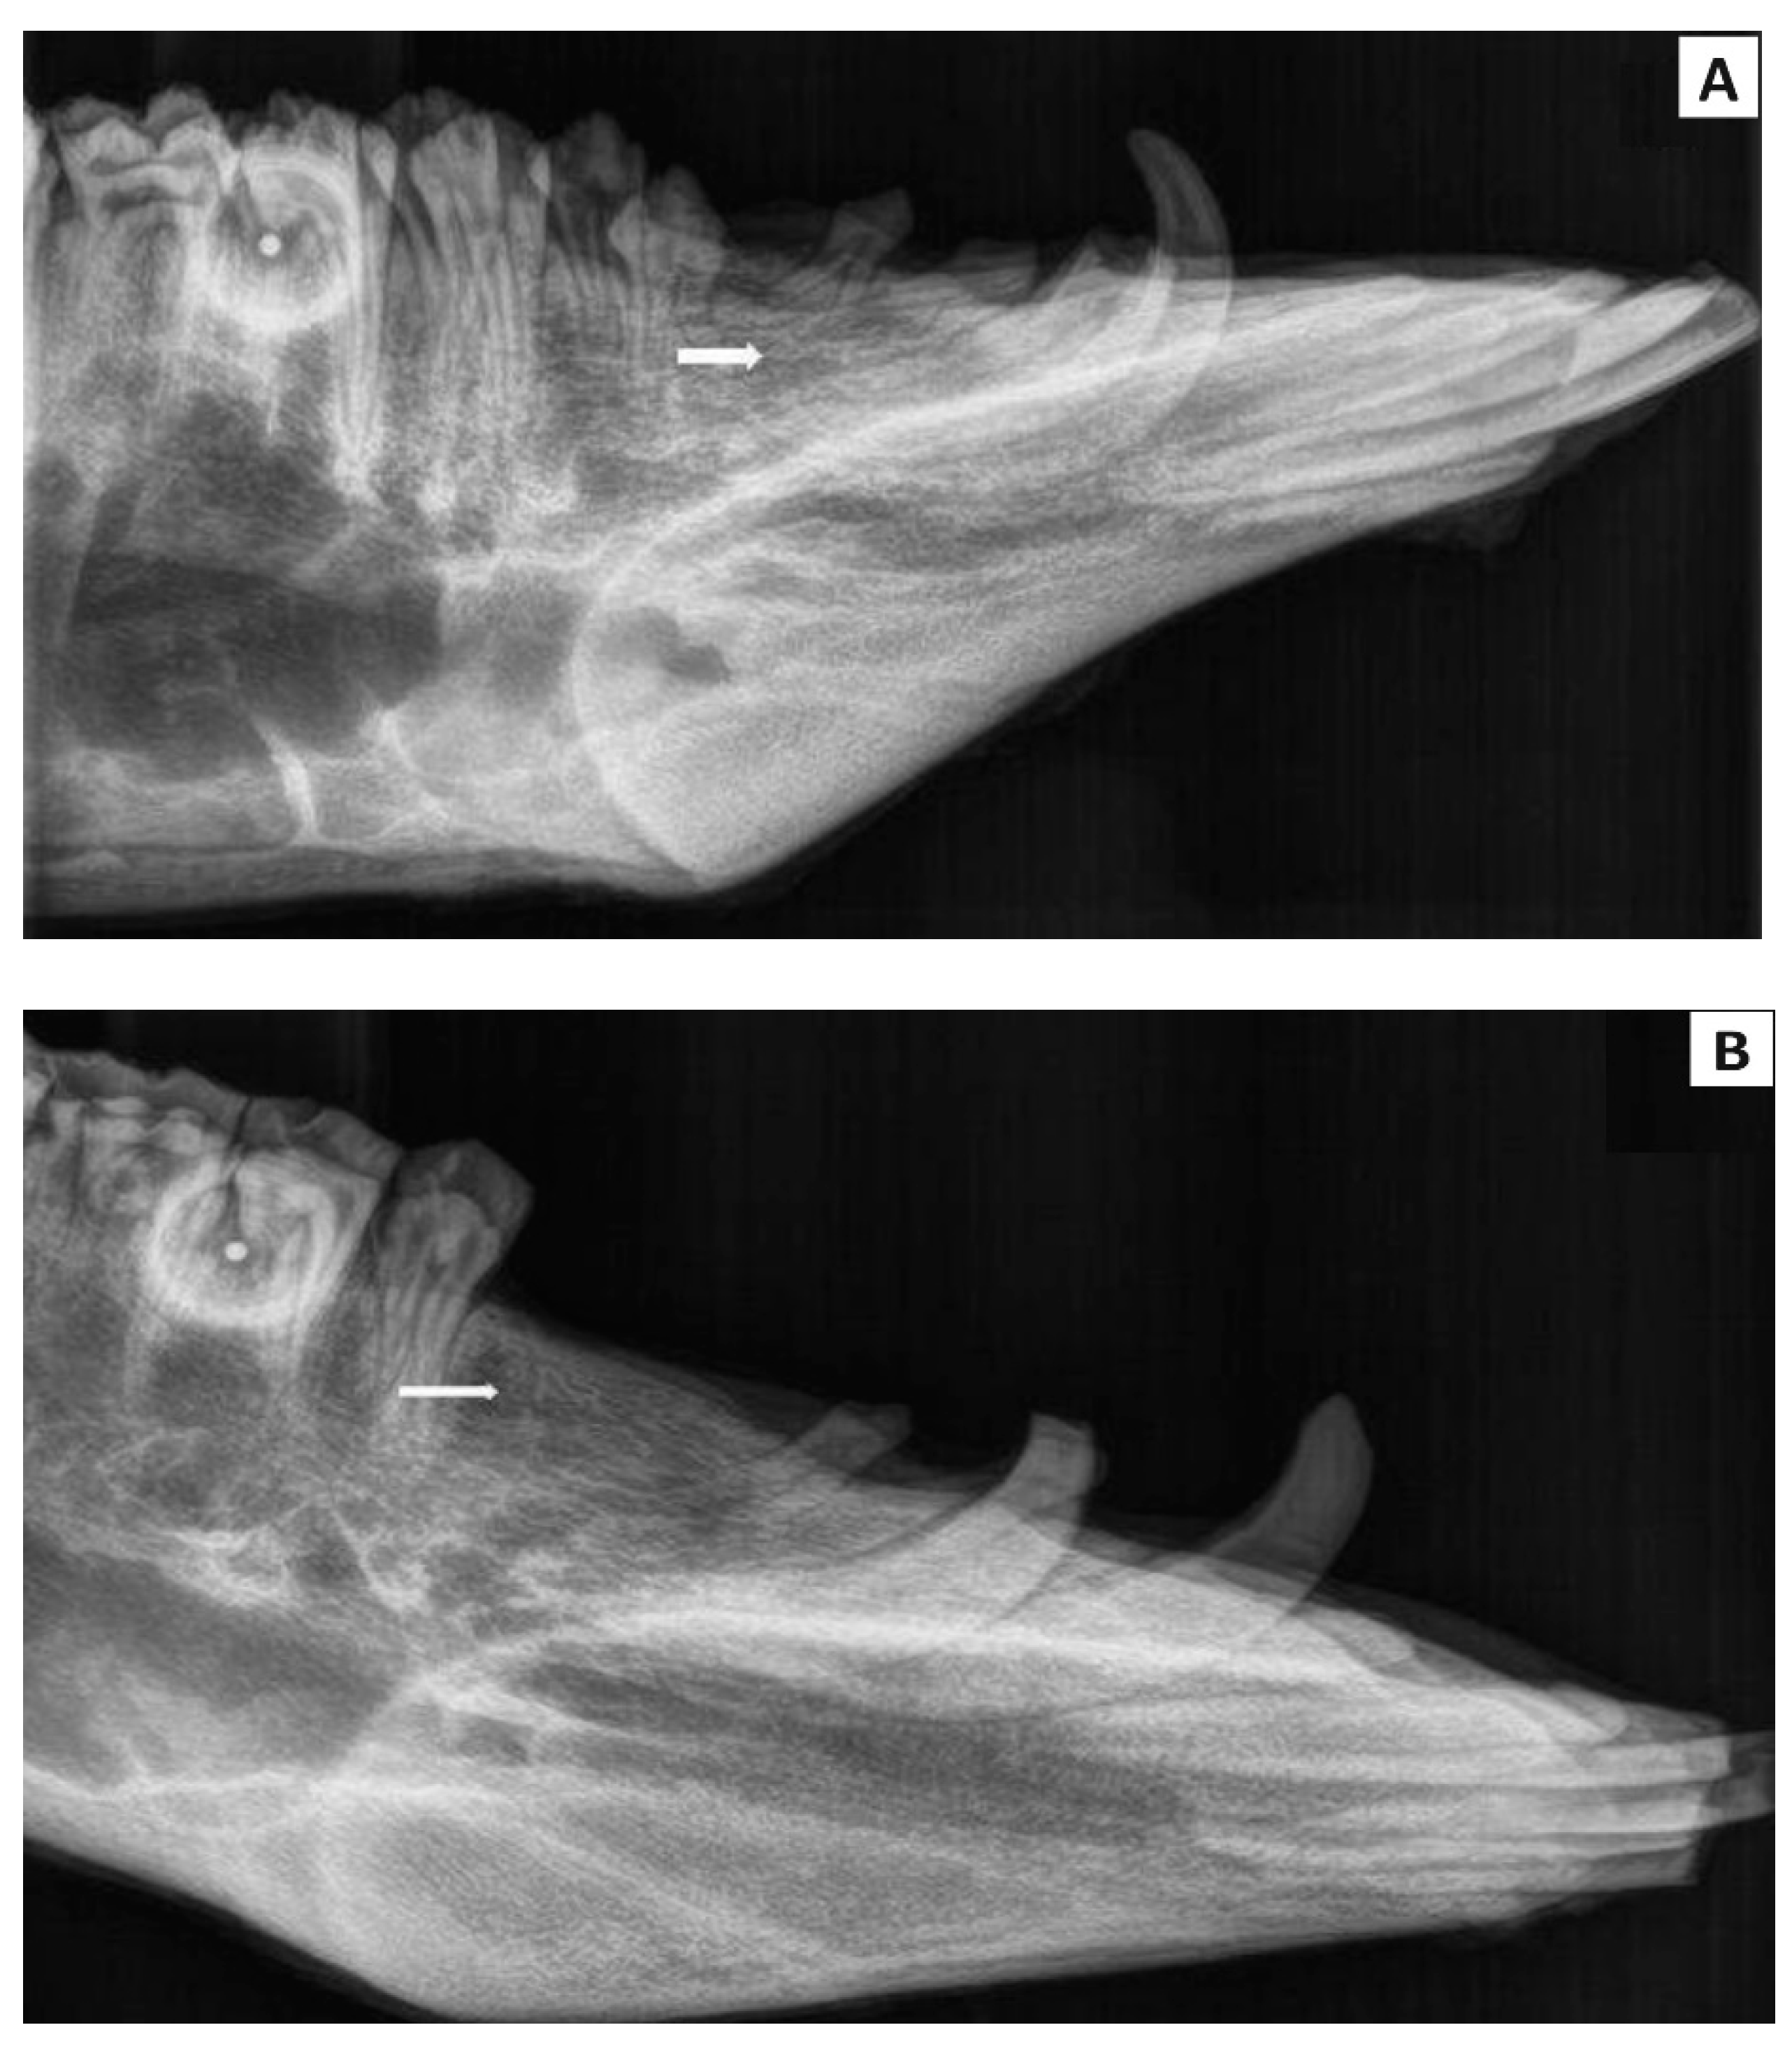

3.5. Radiological Evaluation